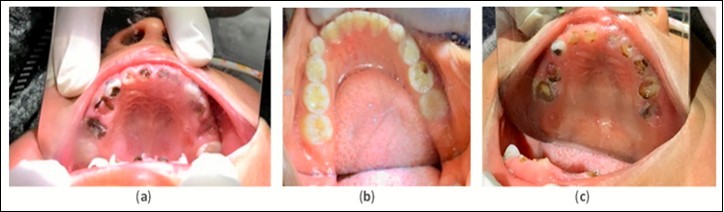

The treatment protocol involved carefully cleaning with a toothbrush and thoroughly drying all cavitated caries lesions using compressed air, followed by the application of 50% SN (Gordon Laboratories) by scrubbing with a microbrush then covering with FV (Centrix, Fluorodose) to protect from saliva contamination. The lesions received three separate treatments over two weeks. This protocol of three treatments was repeated at three and six months. Intraoral images were collected for the maxillary and mandibular arches for all children at each time point (Figure 2 and Figure 3). Emergency services were both conducted on-site and via referral to local professionals. Simple extractions of abscessed teeth with local anesthesia were done on site. Referrals to the local Ministry of Health Dental Clinics were done in cases where endodontics and complex restorative procedures were necessary.

Figure 2.Example pre-treatment intraoral images for Ecuador (a), Ghana (b), and Bolivia (c) at initial evaluation.

The same materials, treatment frequency, and protocol used in Ecuador was replicated in Ghana. Evaluation and treatment were conducted at initial examination and at 12 months. Intraoral images of maxillary and mandibular arches were collected for all patients at each time point (Figure 2 and Figure 3) . At the 12-month visit, the Ghanaian dentist Dr. Ama Ofosu Appiah, our partnering individual, joined the Shoreview team and participated in the project. Her role was to assist in treatment and outcomes documentation. The Shoreview team calibrated this dentist in-person via hands-on training for the application protocol and cavitated caries lesion arrest assessment.

The treatment protocol used in Bolivia differed from what was used in Ecuador and Ghana. The protocol that was used involved the following: carefully clean the cavitated caries lesion using a toothbrush, thoroughly dry using compressed air, apply 38% SDF by scrubbing with a microbrush applicator, then cover with FV to prevent saliva contamination. Since access to electricity was available at the school, mobile dental equipment with a reliable compressed air source was available. This protocol was repeated at the timepoints of 6, 12, 18, 24, 30, and 36 months. Intraoral images of maxillary and mandibular arches were collected for all patients present at 36 months (Figure 2 and Figure 3). Emergency services were both conducted on-site and via referral to local professionals. If a tooth showed signs of being abscessed, it was extracted by Smiles Forever Clinic dentists on site using local anesthesia. Endodontics and complex restorative procedures were referred out to the local hospital dental department or the Smiles Forever Clinic in Cochabamba.

The results discussed below are derived from Table 1. Please review the table for a more comprehensive evaluation of outcomes. Pre-treatment intraoral image examples of cavitated caries lesions in Ecuador, Ghana and Bolivia can be found in Figure 2. An example of arrested cavitated caries lesions can be found in Figure 3. All charted information for all patients was stored securely and confidentially and data was anonymized before evaluation of outcomes.